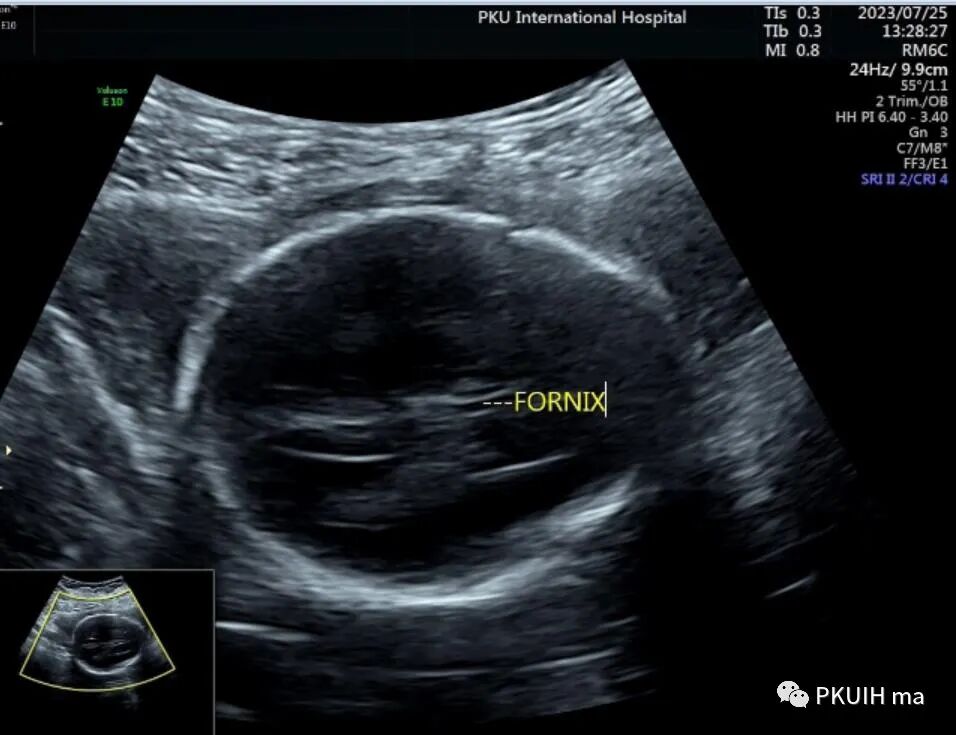

透明隔腔是胎儿中枢神经系统正常发育的一个重要结构。其缺失或形态异常与许多中枢神经系统畸形有关。正常透明隔腔为位于脑中线前部两透明隔间的液体腔,其上方为胼胝体,下方为穹隆,侧壁为透明隔小叶。透明隔腔发育与胼胝体、前联合、穹隆柱密切相关。透明隔腔向后延伸至室间孔,室间孔后方为韦氏腔。

检查中不要把下方的穹窿柱和扩张上抬的三脑室以及融合的侧脑室前角误认为透明隔腔。正常情况下透明隔腔的内径约4-8mm,也有窄的或者宽的,只要形态正常即可,一般大于10mm可以报增宽,小于2mm考虑窄。此时需要关注透明隔腔的形态,一般透明隔腔呈长方形,个别的可以呈三角形,如果左右径大于前后径时认为形态异常。超声显示呈正方形或反长方形、圆形或者是前后径/左右径<1.5时要仔细观察胼胝体,以除外胼胝体发育异常。

妊娠18周前或37周后透明隔腔可以不显示,如果在18-37周之间未发现透明隔腔,要重点观察胼胝体、侧脑室、脑中线、视神经等,最好做个胎儿神经系统筛查,以排除前脑无裂畸形、胼胝体缺失、视-隔发育不良和孤立性透明隔发育不良、脑积水、孔洞脑、脑裂畸形、积水性无脑畸形、脑膨出等。透明隔腔缺失是完全性胼胝体缺失的重要标志,透明隔腔缺失合并“泪滴状”的侧脑室是提示胼胝体缺失的重要线索(如下图),此时一定要重点扫查胼胝体,包括二维及血流等,正中矢状切面是必不可少的扫查。